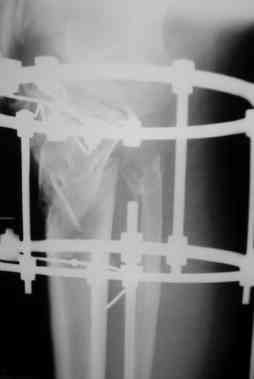

Р-граммы и фото за 4.05.2007 - 7-е сутки после операции.

Ход операции - линейным разрезом по передней поверхности голени обнажена зона ложного сустава большеберцовой кости. От кости отсепарованы медиально м/ткани. Из зоны ложного сустава убраны рубцовые ткани, мобилизован дистальный отломок. По передней поверхности удалены два осколка, связанных грануляциями. Произведено удаление грануляционной ткани из проксимального отломка (на вид сине-серого цвета), "чистого" гноя не было. Затем произведено наложение аппарата и репозиция отломков. По передне-медиальной поверхности образовался дефект до 4х2х2 см + полость в проксимальном отломке. Удаленные осколки очищены от грануляций, уложены в место дефекта, зажаты между отломками. После иссечения раны по передней поверхности, находящейся рядом с операционной раной, последняя ушита с большим натяжением.

Перелом мыщелка сросся. Проксимальный отломок очень порозный.

На перевязках - из раны небольшое кол-во сукровичного отделяемого. Отек голени умеренный, состояние кожи на фото.

Аппарат видел, репозиции не заметил. О "наложенном" аппарате: спицы в проксимальном отломке б\берцовой кости проведены очень низко, и опять только две, как и в первом аппарате. Почему только одна спица в дистальном парафрактурном кольце? Проксимальная база на бедре должна улучшить стабильность проксимального фрагмента tibia? Ничего подобного двумя спицами в одной базе при таком длинном рычаге вы не добьетесь, а вот совсем потерять движения в коленном суставе они почти гарантируют.

О репозиции: мыщелок сросся и слава Богу, но основные отломки фиксированы в вальгусном положении, собственно как и было, это критично. В чем состояла репозиция?